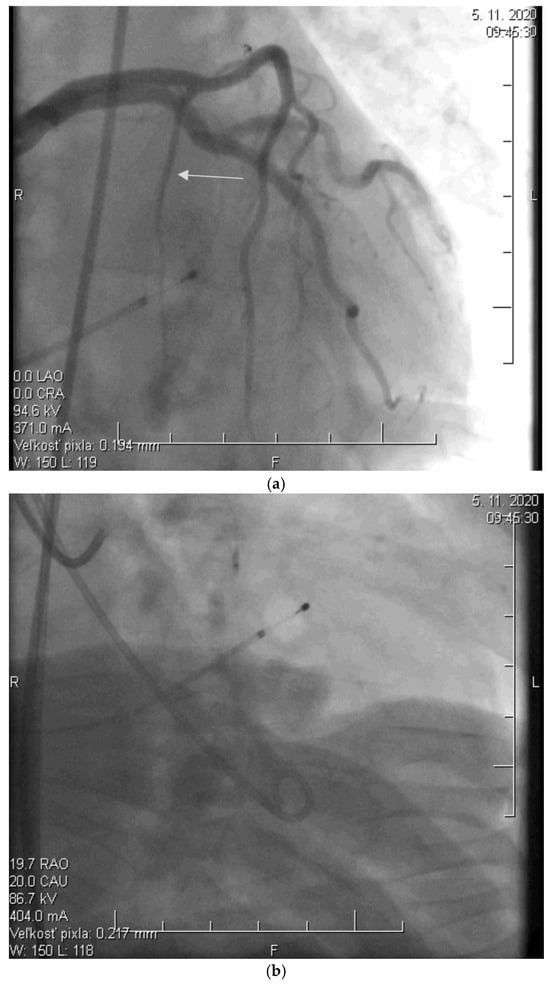

Before the procedure, a temporary pacemaker was inserted into the RV via a venous approach to prevent potential periprocedural conduction disorders. After the pacemaker was placed, selective injection of the left coronary artery was performed via a transfemoral approach to assess the anatomy of its branches (Figure 2a). Using a pigtail catheter introduced into the LV, the pressure gradient between the LV apex and the aorta was measured at rest and after provocation with a ventricular extrasystole, Valsalva maneuver, or, less frequently, nitrate administration.

Figure 2.

(a) Angiographic image of the left coronary artery showing a septal branch (arrow) (photo and copyright: T.P.). (b) Administration of 96% alcohol into the septal branch using an over-the-wire (OTW) balloon catheter (photo and copyright: T.P.). (c) Final effect of ASA with Closure of the Septal Branch (photo and copyright: T.P.).

Subsequently, a specialized over-the-wire balloon catheter was inserted into the septal branch supplying the area contributing to the LVOT narrowing (most commonly the basal interventricular septum. The balloon catheter was inflated to occlude the lumen of this vessel, followed by the injection of an echocontrast agent and echocardiographic assessment of the perfusion area and localization of the selected septal branch (echo-guided approach). After identifying the appropriate septal branch, 96% alcohol in a volume of 2 mL was administered uniformly to all patients according to internal protocol (Figure 2b).

Ten minutes after the alcohol application, the balloon was deflated, and the residual pressure gradient between the LV apex and the aorta was measured at rest and after the aforementioned provocative maneuvers. To conclude the procedure, a selective injection of the LCA was performed to confirm the ablation of the septal branch and exclude potential alcohol leakage into other parts of the coronary circulation, which could cause the no-reflow phenomenon (Figure 2c).